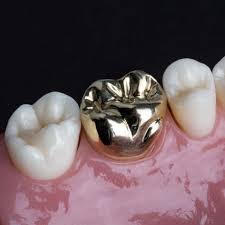

| 골드 | 금 합금 | 생체적합성·마모 적음·정밀도 우수 | 심미성 낮고 비용 높음 | 어금니 |

골드 크라운은 이갈이나 마모 우려가 있는 어금니에 적합하며, 정밀하고 생체 적합성이 뛰어납니다.

- 어금니: 내구성과 적합성 중요 → 골드, PFM, 메탈

- 이갈이·마모 위험: 골드 크라운이 최적

Q1. 골드 크라운도 꼭 하나요?- 이갈이 환자 및 어금니에 매우 추천. 내구성·정밀성 우수.